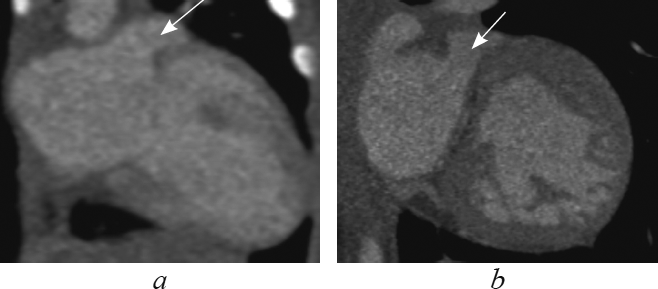

Анатомические признаки ушка, характерного для морфологически правого предсердия (треугольная форма с тупой вершиной, широкое соединение с предсердной полостью, слабо выраженная дольчатость [1, 2, 4, 16]), определяют в реформации по длинной оси приносящего тракта правого желудочка (рис. 1). В этой реформации видно, что при транспозиции морфологически правое предсердие соединяется с морфологически правым желудочком (см. рис. 1, а), а при корригированной транспозиции морфологически правое предсердие — с морфологически левым желудочком (см. рис. 1, b).

Рис. 1. В реформации по длинной оси приносящего тракта правого желудочка ушко морфологически правого предсердия при транспозиции магистральных сосудов (а, стрелка), при корригированной транспозиции магистральных сосудов (b, стрелка)

Fig. 1. Long-axis of right ventricle inflow tract reformation. The eyelet of the morphologically right ventricle in great arteries transposition (a, arrow) and in corrected great arteries transposition (b, arrow)